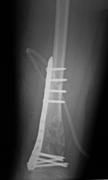

Fibröz displazinin altı aylık aralarla alınacak filmlerlekontrolu yapılır. Bifosfanatlar medikal tedavide altın standarttır. Patolojik kırık veya patolojik kırık gelişme ihtimali yüksek olduğunda kanal içi çivileme ile tedavi edilir. Deformite geliştiğinde düzeltici osteotomi ve internal osteosentez uygulanır. Cerrahi tedavide; küretaj +grefonaj, yüksek nüks nedeni ile gözardı edilir, kanal içi osteosentez uygulanır. Ayrıca deformitenin gelişmesini engellemek için de geniş lezyonlarda koruyucu internal fiksasyon da yapılır. Büyüme kıkırdaklarının aktif olduğu dönemlerde intramedüller çivileme bu bölgelere zarar verebilir. Tedavide amaç deformitelerin oluşmasını engellemek ve var olanı düzeltmektir. Monostotik formlarda %0,4 oranında kötü huylu tümöre (malignite) dönüş bildirilmiştir.